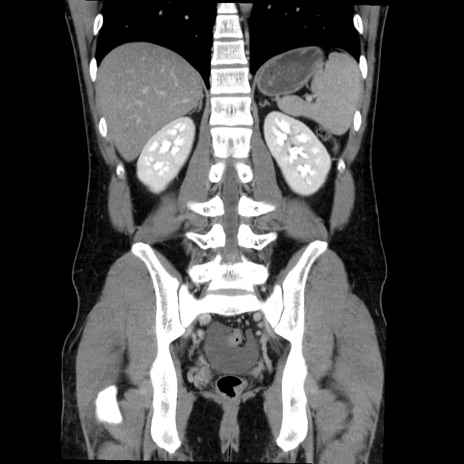

症例36(冠状断像)

【症例】20歳代 男性

【主訴】心窩部痛

【現病歴】今朝より上腹部痛あり。一旦軽快していたが再度出現したため救急要請。昨日夕に白身の魚を含む刺身を食べた。

【身体所見】BP 136/89mmHg、HR 74/min、BT 37.0℃、腹部:膨満、軟、心窩部に圧痛あり。反跳痛なし、筋性防御なし、腸雑音やや亢進あり。

【データ】WBC 17700、CRP 0.48